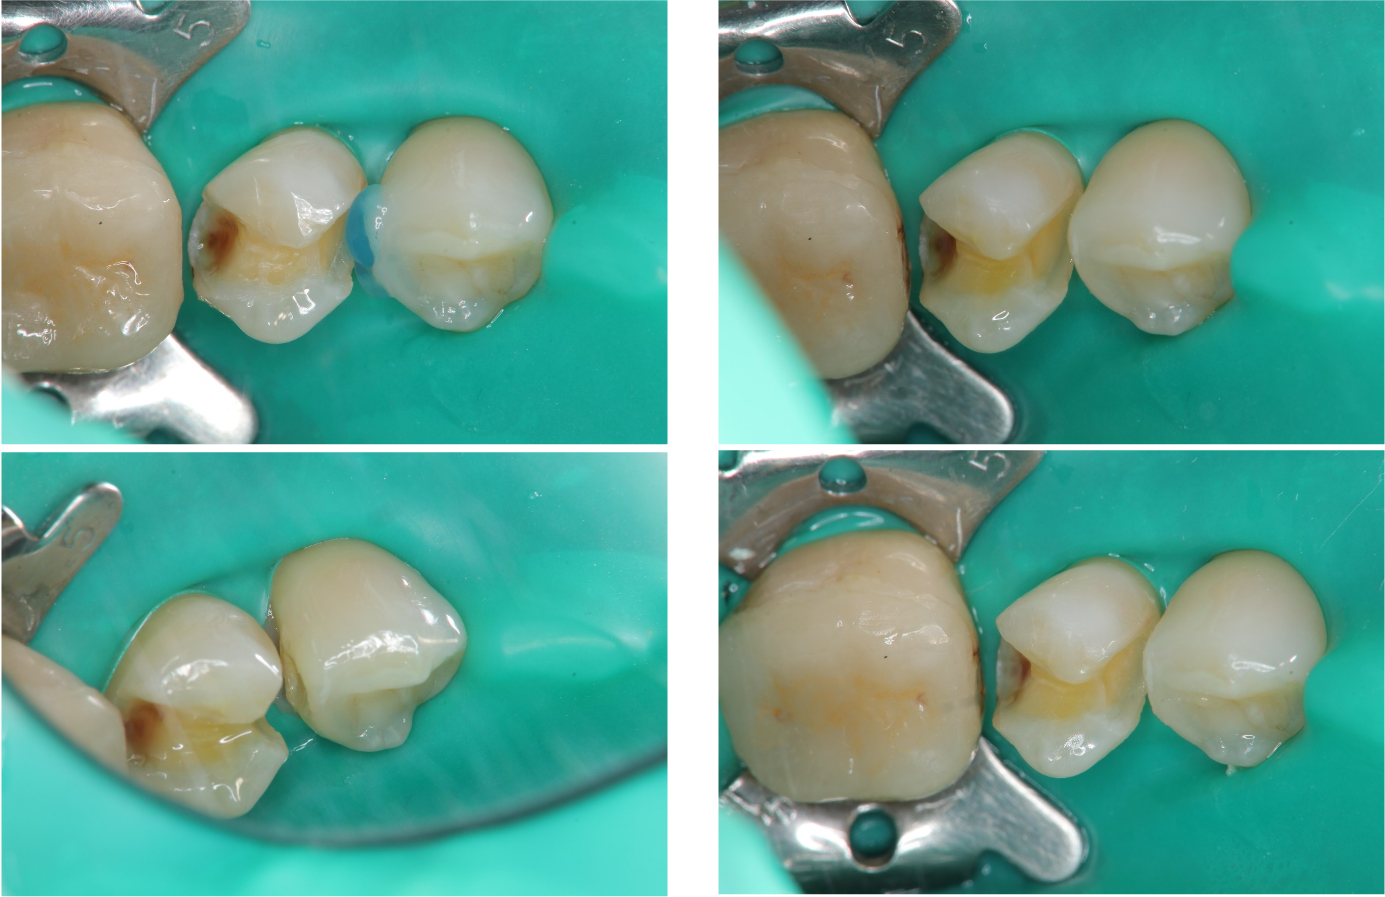

而過程中,在其他牙之鄰接面,往往有其他隱藏的蛀牙,由於瓷塊製備時,鄰接面磨開,因此鄰牙之牙相對容易以複合樹脂復形。

鄰牙蛀牙以複合樹脂復形